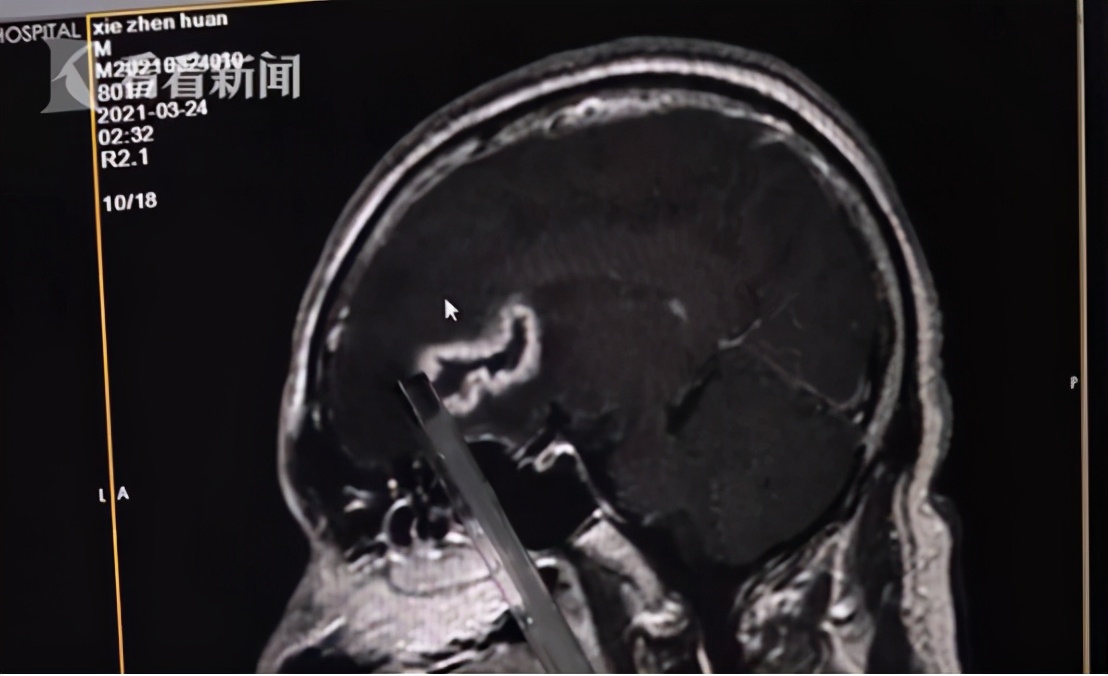

很多人都说,牙痛不是病,痛起来拿你命。生活中,拔牙是一件再正常不过的事情,但正是小小的拔牙,有时候也可能危及生命广州的姚先生就是如此,简单的拔牙却让他的大脑抽出了近30毫升的腥臭脓液。

半年前,姚先生因为牙痛而拔掉了自己的一个蛀牙,在姚先生的口腔内遗留了一个较大的牙缝,吃饭的时候经常塞牙,姚先生便养成了吸牙的习惯,但长此以往,早吃口腔内的细菌感染到了颅内,引起了颅内细菌感染。